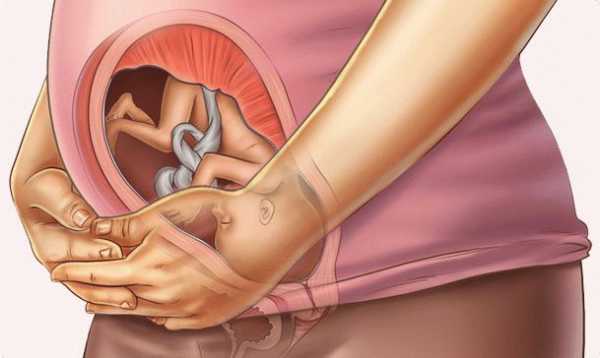

По мере роста у него начинает формироваться поза эмбриона. То есть, его ручки и ножки плотно прижаты к телу и перекрещены между собой. Он продолжает совершать дыхательные движения, заглатывая и вдыхая амниотическую жидкость. Извлекая необходимую порцию воды, сахара и других необходимых микроэлементов, остатки превращаются в первый кал – меконий.

Как должен быть расположен плод?

Начиная с 27-28 недели беременности может быть поставлен диагноз тазовое предлежание плода. Раньше этого срока подобный диагноз не ставится, так как ребенок очень мал и может довольно часто переворачиваться. Сейчас движения плода стеснены, внутри матки ему уже не так просторно как раньше. Считается, что к началу третьего триместра плод должен располагаться головкой вниз. Однако, диагноз пока только предварительный. Врач внимательно будет следить за положением малыша до самых родов.

Как показывает практика, некоторые детки принимают правильное положение только на 9 месяце течения беременности. В случае тазового предлежания врач может посоветовать специальные упражнения, чтобы стимулировать малыша перевернуться. Следует внимательно слушать и выполнять все назначения своего врача.

На 27 неделе беременности растущий плод может менять свое положение. Не столь важно, как расположен ребенок, поскольку он переворачивается несколько раз за день. С утра находится вниз головкой, а вечером – наоборот. К моменту родов карапуз расположится правильно.

В среднем на сроке 27 недель рост плода составляет около 35 см и более, вес достигает 1000 г. Его ножки скрещены, а ручки прижаты к груди. Что, однако, не мешает ему переворачиваться – места в матке для свободных движений еще достаточно. Эти упражнения становятся все ощутимее и заметнее внешне, когда на животе беременной выпирает ладошка или маленькая пятка. На этом сроке малыш обычно занимает положение головой вниз, в котором остается до момента рождения.

Ваш кроха растёт и начинает ощущать некоторую тесноту маточной полости. Подросшие ножки и ручки малышу буквально некуда девать. Так что в покое кроха всё чаще занимает оптимальную для плода позу: подтягивает скрещённые ножки и ручки к животику и груди. Когда придёт время родов, именно такое положение тела (головкой вниз) позволяет ребёнку нормально, без осложнений пройти через родовые пути матери.

Сейчас плод необязательно расположен на 100% правильно. Он может устроиться и поперёк матки, и как-либо по диагонали. При осмотре врач может сказать вам, что головка плода – прямо под вашими рёбрами. Не пугайтесь. К моменту родов малыш ещё успеет повернуться как положено.

К концу шестого месяца периода вынашивания малыш имеет крупные размеры тела, поэтому он испытывает трудности во время движений. Ребенку становится тесно в матке, он все реже поворачивается вокруг своей оси. Чаще всего шевеления плода на данном сроке связаны с движением ручек, ножек и шеи.

В начале третьего триместра ребенок умеет совершать множество движений, свойственных новорожденному. Малыш икает, сосет пальчик на кистях рук, играет с пуповиной, закрывает лицо руками. Плод отворачивается от источника яркого света или громкого шума.